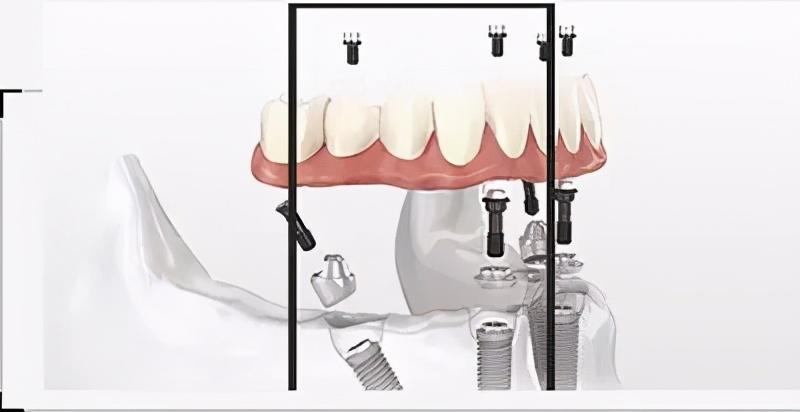

注明:此植體只是模擬位置,不做確切種植位置。

step3

等待骨結(jié)合期

這個時間的長短因人、因種植系統(tǒng)而異。有的人、有的種植牙系統(tǒng)要2--3個月;骨件較差有的需要約半年時間。